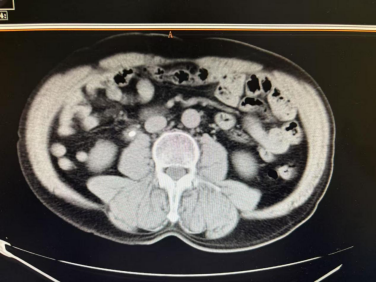

近日,一位家住经开区的马先生,因突发右侧腰部剧痛,在外院经超声检查确诊为“右侧输尿管上段结石(约11mm×4mm)并右肾积水”。由于结石体积较大,外院建议其行钬激光碎石治疗。然而,面对三甲医院较高的手术费用,马先生一度犹豫,选择返回家中。

入院后,我院泌尿外科团队迅速为马先生完善了术前准备。凭借丰富的经验和完善的设备,专家团队很快为其成功实施了“经尿道输尿管软镜激光碎石术”。手术过程顺利,术中即将堵塞输尿管的结石完全粉碎并清除。术后复查显示,输尿管内结石已消失无踪,解除了肾积水风险,马先生对治疗效果表示十分满意。